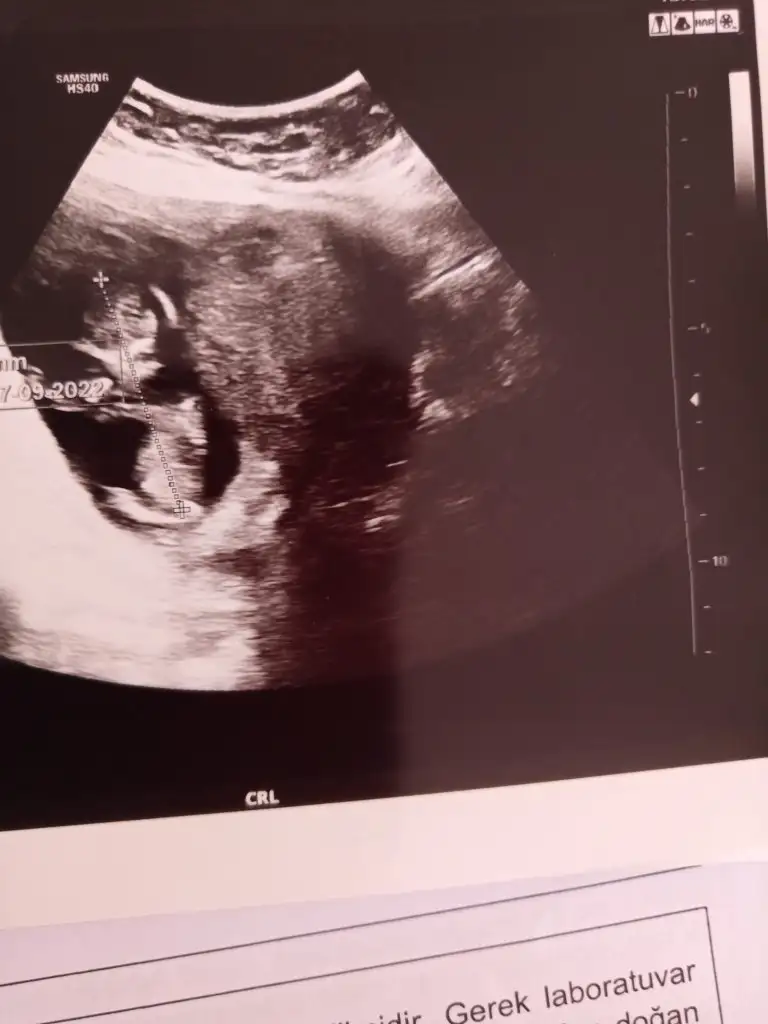

Ben çıktım şükürler olsun tam 12 haftalikmis folik asiti kesti doktor.d vitamini damla,demir ilaci ferrum, bide decavit vitamin başladı.ayrica akıntım olduğu için flora duzenleyici bir probiyotik aldirdi..ikili testin kararini tamamen bana birakti ben de kabul etmedim ikili testi yaptirmayacagm Allahtan gelen her şeye raziyim dedim.ve bir ay sonraya kadar simdilik boyle